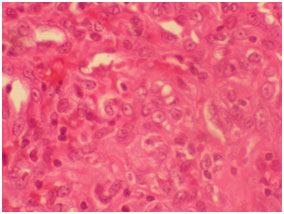

On microscopic examination, there were cavernous vascular spaces, solid spindle cells attached to vessel walls and vacuolated epitheloidendothelial cells [Table/Fig-5,6]. The lesion was well circumscribed, highly cellular with vascular proliferation and slit like spaces [Table/Fig-5,7]. There were few lymphocytes and eosinophils. Larger thin walled vessels with RBCs and areas of hemorrhage were also appreciated. The lesion did not show any cellular atypia and was well circumscribed without infiltration to surrounding structures. Histopathological diagnosis of vascular lesion i.e., spindle cell haemangioma was given. Immunohistochemistry (IHC) was done for the markers CD- 34 and CD- 31 for evaluation of origin of these spindle cells which were triple positive. Pericytes with surrounding blood vessels, split like vascular spaces lined by endothelial cells were positive for CD-34 and cells in vascular channels near endothelial lining were positive for CD 31 [Table/Fig-8] [1].

H&E 40X Histopathology showing epitheloid enodethelial cells with vacuolations